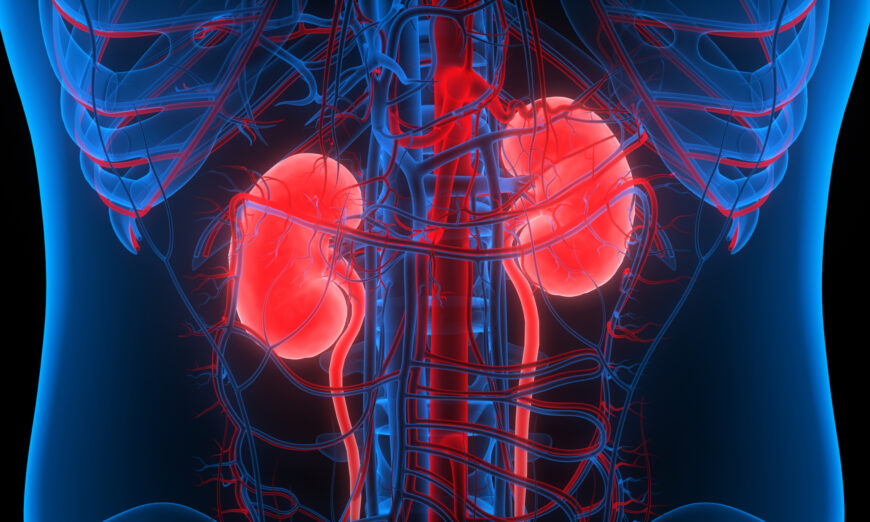

Lọc thận có phải là gánh nặng cả đời không?

Chạy thận nhân tạo đem lại những rắc rối cho bệnh nhân thận kinh niên. Đông y có thể giải quyết điều này?